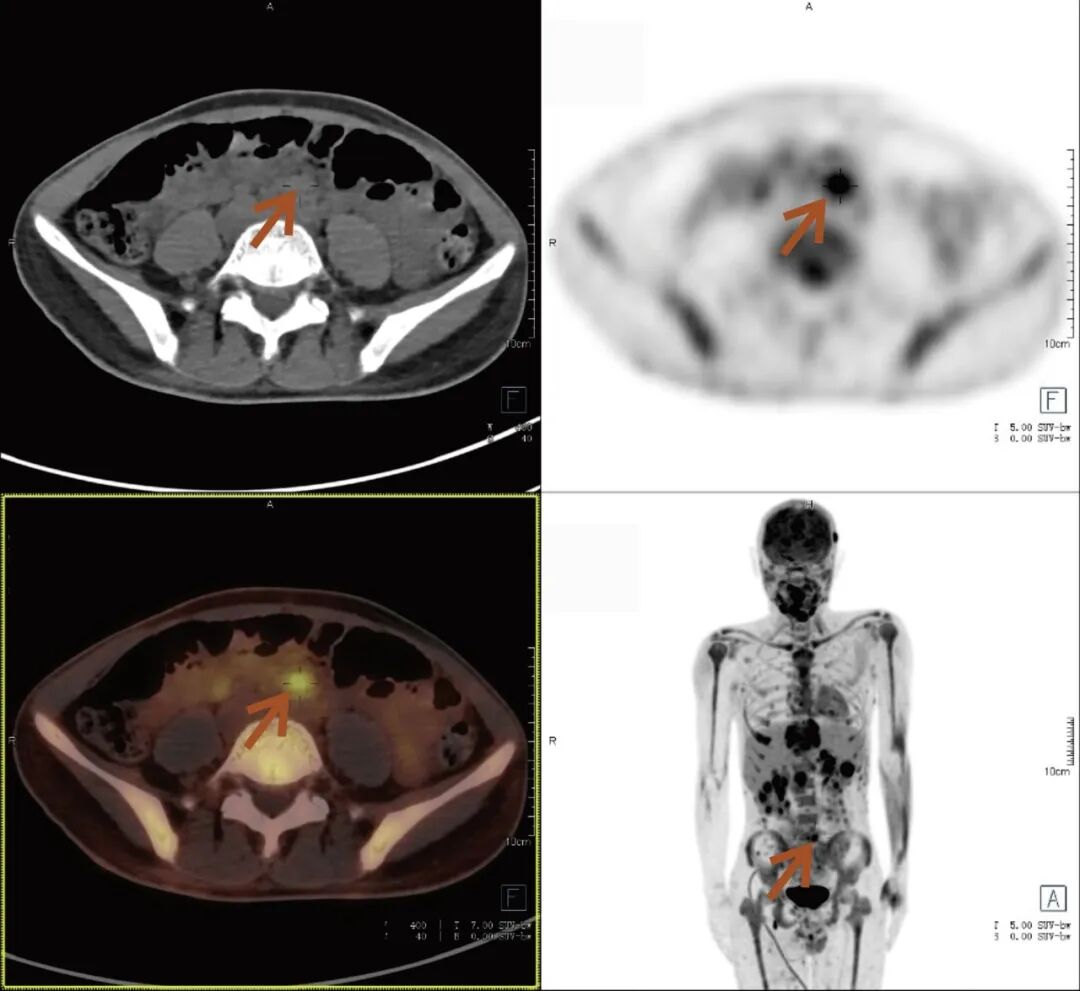

张先生(化名),因持续3个多月的腹痛、腰痛在外院就诊。初始CT检查发现其胸11椎体骨质破坏伴周围软组织肿胀,考虑为“脊柱结核”等感染性病变,并接受了中药治疗。然而,两个月后,张先生又出现了新的症状——牙痛。 经病理活检及免疫组化检查,最终确诊为极为罕见的Erdheim-Chester病。为全面评估这一可累及全身多系统疾病的侵犯范围、明确病灶活动性,并为制定精准治疗方案提供依据,张先生进行了全身PET/CT检查。 PET/CT检查图像: PET/CT检查结果: (1)中轴骨及四肢骨广泛FDG代谢活跃伴信号异常;其中胸10、胸11椎体病灶周围软组织增厚,累及邻近椎管内及双侧椎间孔、双侧胸膜,并与主动脉分界不清。 (2)全身皮下及肌层内多发结节及肿块,FDG代谢活跃;全身软组织广泛肿胀。 (3)鼻咽各壁增厚,顶后壁为著,FDG代谢活跃。 (4)甲状腺多发结节,FDG代谢活跃;双肾及胰腺多发结节及肿块,FDG代谢活跃;双侧阴囊内异常信号伴FDG代谢活跃; (5)左侧锁骨上窝、纵隔内(2L区、3A区)、降主动脉旁、左侧横膈前组、右侧腋窝、左肾周间隙、肠系膜区、双侧髂血管旁多发淋巴结,FDG代谢活跃; (6)心包局部呈结节状稍增厚,FDG代谢轻度活跃; 综上,结合临床,均考虑Erdheim-Chester病所致。 此次PET/CT不仅证实了已知的脊柱病变,更一次性揭示了临床尚未怀疑的、广泛存在于内脏、淋巴结及软组织的隐匿病灶,为疾病分期与治疗提供了决定性依据。